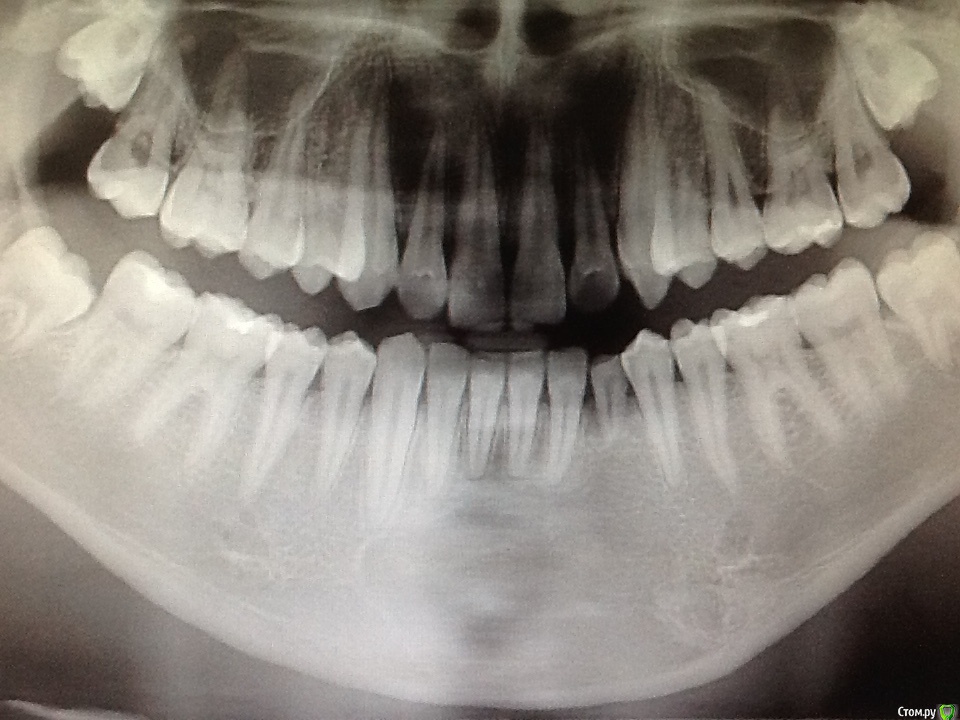

Л Ю С Я Опубликовано 5 сентября, 2016 Автор Поделиться Опубликовано 5 сентября, 2016 Если кому интересноСейчас парню 18 лет, термотест всех нижних резцов кроме 4.2 положительный, даже молочного клыка. 4.2 - решили наблюдать, перкуссия б. б, цвет не изменён. Надеюсь, что просто не восстановилась иннервация. Что скажите, когда можно делать имплант на место молочного резца? 2 Ссылка на комментарий

Чертков Александр Опубликовано 5 сентября, 2016 Поделиться Опубликовано 5 сентября, 2016 когда можно делать имплант на место молочного резца? КТ бы глянуть...и тогда ясно станет когда имплантат 1 Ссылка на комментарий